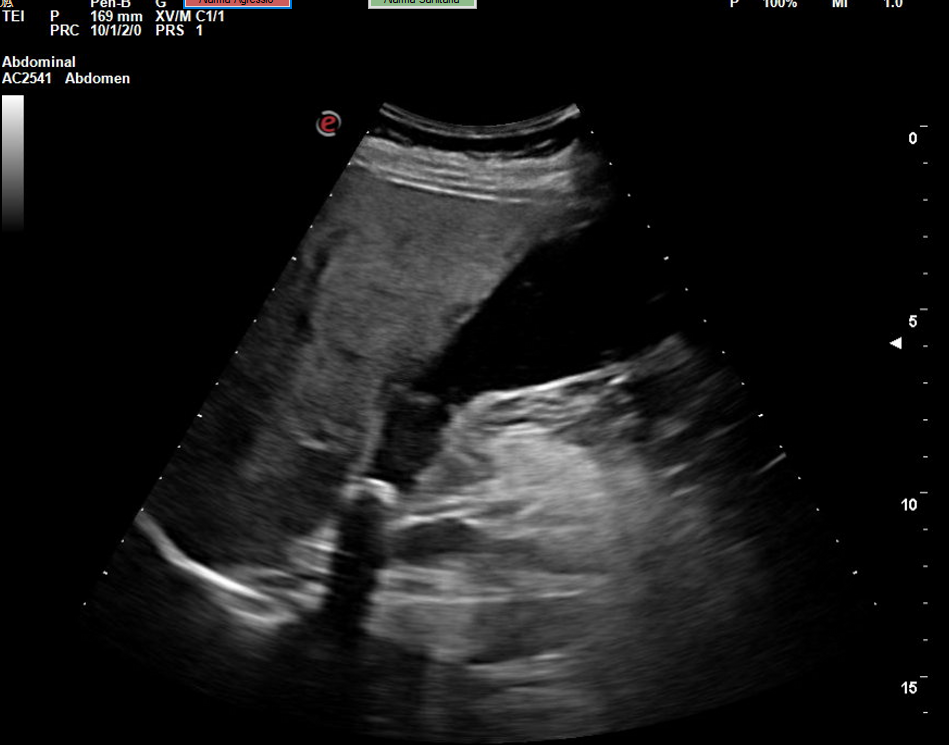

Se realiza la ecografía abdominal en el ambulatorio, donde se objetiva colelitiasis con el colédoco en el límite superior de la normalidad (4,4 mm), también presenta esteatosis hepática grado I. El resto de la ecografía no presenta hallazgos de interés.

Colelitiasis con colédoco en el límite de la normalidad.